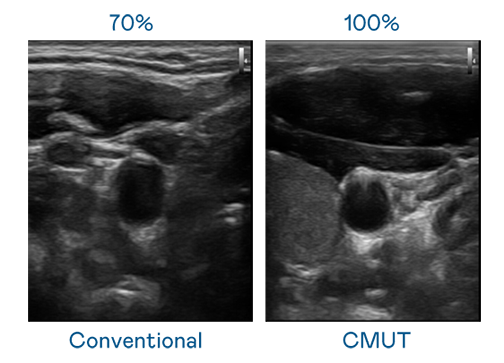

CMUT 技術是一種用電容式微機電元件來產生超音波訊號的技術。與傳統 PZT 壓電式技術相比,CMUT 頻寬增加 30%,更寬頻的超音波訊號讓影像解析度大幅提升,是實現高影像品質醫療超音波掃描、促進精準醫療發展的關鍵技術。

超音波影像的解析度高低,首先取決於探頭能發出的訊號頻寬。星空电子 CMUT 可提供高清晰的超音波訊號,提供高頻寬、高靈敏度、影像紋理細節更高的超音波影像,協助醫護人員縮短影像判讀時間及利用精準的醫療影像進行診斷。